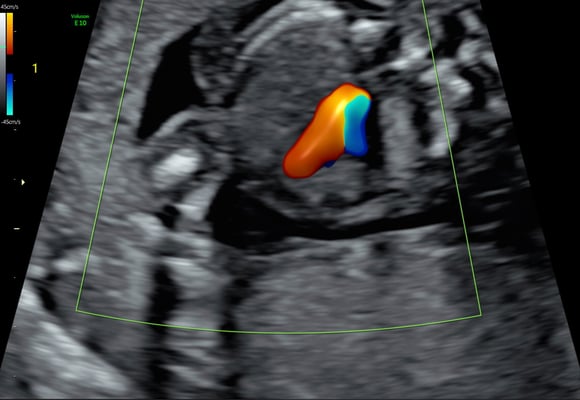

Im Rahmen des traditionellen Dopplersymposiums in Salzburg, welches heuer von 28. bis 30. April 2023 stattfindet, wird in diesem Jahr erstmals ein Fokustag in fetaler Echokardiographie am Samstag, 29. April 2023, angeboten.

Ziel dieser Veranstaltung ist es, innerhalb eines Tages einen umfassenden Einblick in das fetale Herz zu bekommen. Von der Embryologie zur sonographischen Darstellung der normalen Entwicklung, von der Genetik zur sonographischen Erkennung fetaler Herzfehlbildungen, von der Indikation für fetale Echokardiographie zur Indikation pränataler Intervention bei Vorliegen spezieller Herzfehler. Renommierte ExpertInnen mit langjähriger Erfahrung berichten aus ihrer täglichen Arbeit in Praxis- und Klinikalltag. Die KursteilnehmerInnen bekommen im Rahmen von Hands-on-Übungen die Möglichkeit unter Supervision die Standardeinstellungen der fetalen Echokardiographie an Schwangeren im 2. und 3. Trimenon zu erlernen.